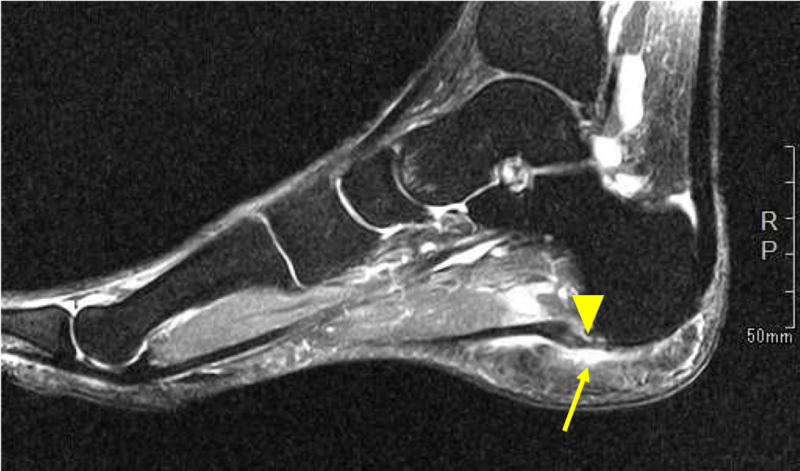

例)足底腱膜炎

足底腱膜の変性(腫れ)の評価(矢頭)

レントゲンやMRI、超音波診断装置でどこが病因なのかを探りその部位に注射を行います。